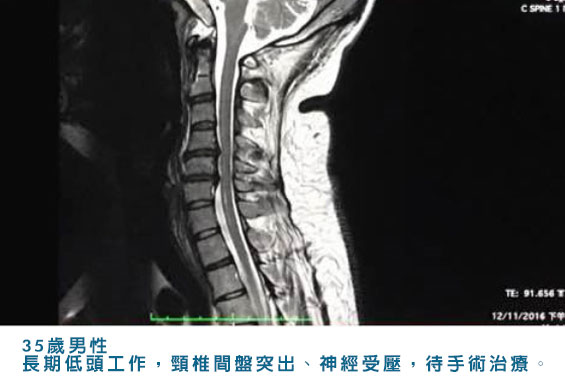

近十幾二十年來,因為電腦和智能手機的普及,低頭族的頸椎病變成為一個日益普遍的健康問題,而且這種情況早已經開始影響我們的兒童和青少年。然而根據筆者多年來的臨床經驗,頸椎病變的症狀通常不明顯,患者可能不會感到頸痛,因而無法察覺自己存有頸椎問題。再者許多患者在頸椎問題上面臨的不僅僅是頸痛或者四肢麻痺的症狀,而是一系列意想不到和出乎意料之外的奇怪症狀,包括頭痛、頭暈、耳鳴、胃部不適、情緒變化、心悸等等的迷走神經症狀。

頸椎病變和腰椎病變的原因相同,主要是勞損、退化和受傷三大因素。近年來頸椎勞損是普遍的主因,這與不分世代長期使用電腦、手機等電子產品的低頭族生活方式有密切關係。除此之外不良的坐姿、睡眠姿勢、缺乏運動, 都會加速頸椎勞損、退化和骨刺增生。人體七節頸椎骨之間中的椎間盤就像汽車輪胎的功能,具有緩衝壓力和吸收震力的作用。

但隨着低頭族頸部長期勞損及人體自然的老化退化,椎間盤會失去水分,就如同輪胎漏氣一樣,失去緩壓吸震的原有功效。當輕微受傷時,椎間盤周邊的保護纖維環會撕裂, 猶如車胎爆裂般導致位於椎間盤中心的凝膠狀結構突出並壓迫脊髓或神經。隨着年齡增長椎間盤失去緩壓吸震功效,會加重頸椎節骨間磨損的情況導致骨刺這類病理變化,骨刺亦會壓迫脊髓或神經。